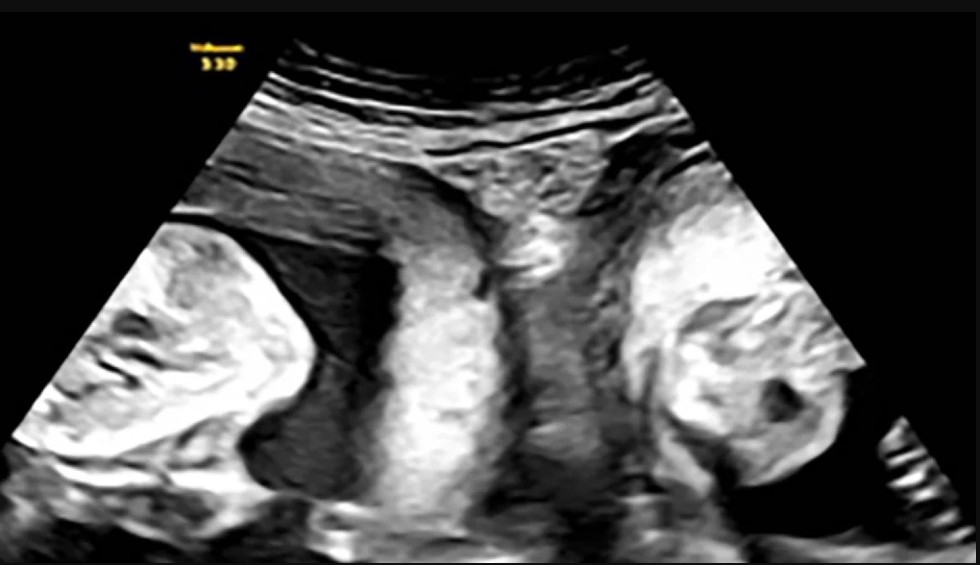

Τον Ιανουάριο, όμως, η Li έμεινε ξανά έγκυος και ανακάλυψε κατά τη διάρκεια ενός υπερηχογραφήματος ότι κυοφορούσε δίδυμα - ένα σε κάθε μήτρα και οι γιατροί του νοσοκομείου «έπεσαν» πάνω στο περιστατικό για να εξασφαλίσουν την επιτυχία της εγκυμοσύνης.

Μετά από στενή ιατρική παρακολούθηση, η γυναίκα κατάφερε να γεννήσει ένα αγόρι βάρους 3,3 κιλών και ένα κορίτσι βάρους 2,4 κιλών, σύμφωνα με το νοσοκομείο.